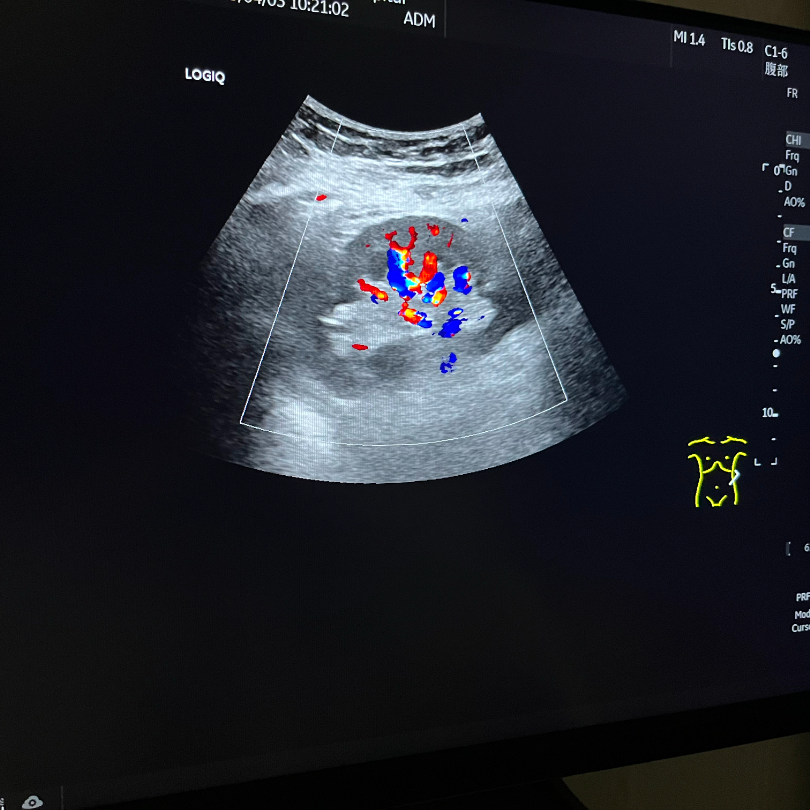

GE LOGIQ-Fortis Plus在甲状腺、乳腺、双下肢、颈部血管等检查项目方面有明显优势,对微血流的显示和弹性成像技术有全新的视野,图像更清晰细腻,血流显示立体逼真,能够实现二维条件下血流的“立体浮雕式”呈现,减少彩色血流闪烁,增强细微血管的可视化成像效果有利于临近交叉血管的边界识别。